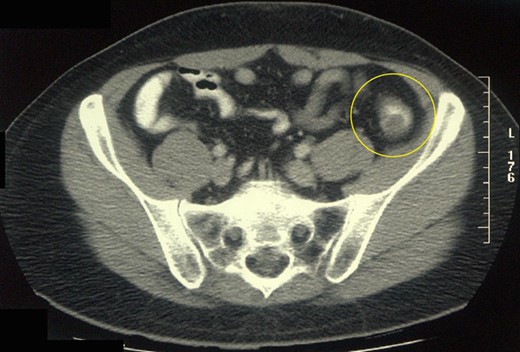

A 43-year-old man presented with seven months of intermittent lower abdominal pain and altered bowel habit. The patient denied having similar symptoms in the past or any history of abdominal surgery. He had no past medical history or familial history of colorectal malignancy. On presentation, he appears well with no tenderness or palpable masses on abdominal examination. A computed tomography of the abdomen and pelvis demonstrated a 13 × 10 × 10 mm3 ovoid lesion in the distal descending colon and no evidence obstruction and associated regional lymphadenopathy (Fig. 1). A colonoscopy performed confirmed the ovoid mass, for which an inverted diverticulum was initially suspected (Fig. 2). Mucosal biopsies did not demonstrate any pathological changes. The patient underwent laparoscopic high anterior resection with an uncomplicated post-operative course and a rapid recovery.

Abdominal CT scan of the patient showing a space-occupying lesion in the distal descending colon.